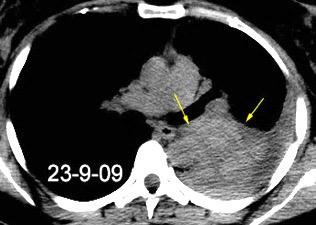

40. EMPIEMA PLEURAL. ORIGEN HEPÁTICO

Colecciones “inflamatorias” abdominales llegan al tórax vía el hiato esofágico o por vía transdiafragmática

Afectación transdiafragmática: 5,6-43,7% de quistes hepáticos. “Área desnuda” del hígado.

Panda A et al. “Straddling Across Boundaries”. Thoracoabdominal Lesions: Spectrum and Pattern Approach. Curr Probl Diagn Radiol. 2015 Área desnuda. El hígado en contacto directo con el tendón central del diafragma. Contiene el hiato de VCI.